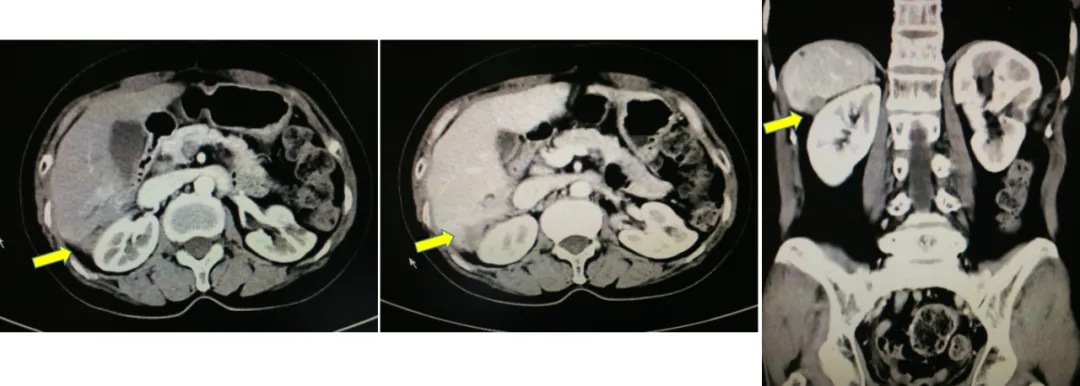

2016.10.26行三次减瘤术(乙状结肠部分切除侧侧吻合+腹盆腔减瘤+腹膜后淋巴结切除),术后无肉眼残留。

术中所见